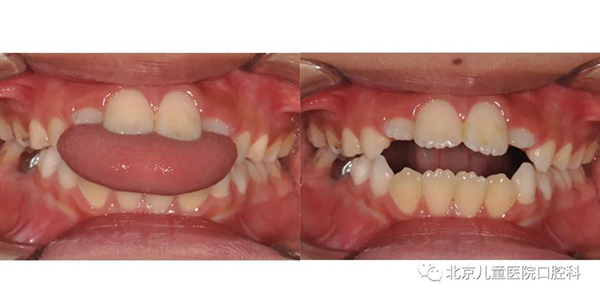

这个阶段是孩子生长发育的高峰期,颌骨具有很高的生长潜能,所以也是对面容改善最有利的一个阶段。对于牙齿反合的孩子来说,这个阶段是治疗的关键期,对于解除牙齿的反合、改善“弯月脸”来说至关重要。

“弯月脸”下颌相对突出而上颌相对后缩,牙齿也是下牙突出

有的孩子存在一些口腔不良习惯,会影响牙齿的咬合和面部美观,比如口呼吸会导致下颌逐渐后缩、上牙逐渐前突;吐舌习惯会让牙齿前牙开咬,影响进食和发音。

口呼吸习惯导致下颌后缩、上牙前突

吐舌习惯导致前牙开合咬不上